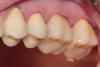

dr.moskvichev Опубликовано 17 августа, 2013 Поделиться Опубликовано 17 августа, 2013 После удаления композита и кариеса выбор пал на керамические вкладки. Временные реставрации изготовил из Protemp 4 по ключу из силикона, обработал дентин-герметизующим ликвидом, дебондинг,одномоментный двухслойный оттиск Express, временная цементировка на Temp NE. Техническая работа заняла неделю Времяшки выдержали, зубы не болели, незначительная гиперестезия к концу недели. Фиксировал на вариолинк 2. На следующий день после фиксации отмечалась слабовыраженная гиперестезия, которая исчезла на второй день. Основной вопрос: Будут ли такие конструкции состоятельные в отношении прочности(особенно при боковой нагрузке) в отдаленные результаты? Вопрос назрел в связи с большим межокклюзионным растоянием между буграми препарированных зубов и антагонистов (коронки м.к). Хватит ли силы адгезии для удержания таких крупных вкладок? Спасибо за внимание. 11 Ссылка на комментарий

dr.moskvichev Опубликовано 17 августа, 2013 Автор Поделиться Опубликовано 17 августа, 2013 (изменено) Согласен. Редукцию небных всё же сделал бы,вероятно. Так,как в кейсе, не точил бы,скорее - надстроил бы кором - и запилил под полные коронки,чем так. P.s. Но кейс аккуратный.Редукция небных практически до десневого уровня, что обусловлено большей окклюзионной нагрузкой на них. А вот с щечной стороны пожалел ткани- в ущерб эстетике, но с минимальной инвазией. По цвету получилось приемлимо, после полировки граница и переход видны минимально. Изменено 17 августа, 2013 пользователем dr.moskvichev Ссылка на комментарий

dr.moskvichev Опубликовано 17 августа, 2013 Автор Поделиться Опубликовано 17 августа, 2013 ТС,чем Вы руководствовались,оставляя дентиновые рога,безбожно скосив эмаль?Как раз-таки макромеханической ретенцией....Щечные бугры имеют прямой контакт с антагонистами, выводить их вестибулярнее было бы не правильно. Не хотел размещать границу препа в оклюзионных точках вот и все...Ведь здесь не классическая ортогнатия.. Классические полости "Бородатого" не учитывают отклонения в окклюзии. Уступ с вестибулярной стороны и рога именно для улучшения макромеханической ретенции а так же для увеличения площади адгезивной фиксации..... Ссылка на комментарий